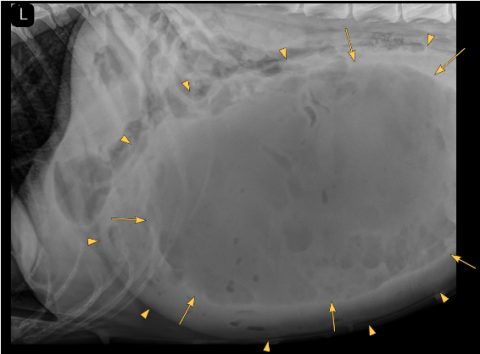

There is severe distention of the abdomen. As far as included the extra-abdominal soft tissues are within normal limits. There are 8 lumbar vertebrae, otherwise the bony structures are within normal limits.

A large well-defined, rounded soft tissue mass is noted in the caudal mid and cranial abdomen. The mass is filled with combination of fluid ( yellow arrow points) and gas (yellow arrows) and originating from the uterus.

The mass is displacing the gastrointestinal tract dorsally, cranially and laterally.

Large fluid and gas-filled mass in the caudal, mid and cranial abdomen originating from the uterus (emphysematous pyometra). Considering the shape of the mass a torsion is suspected.